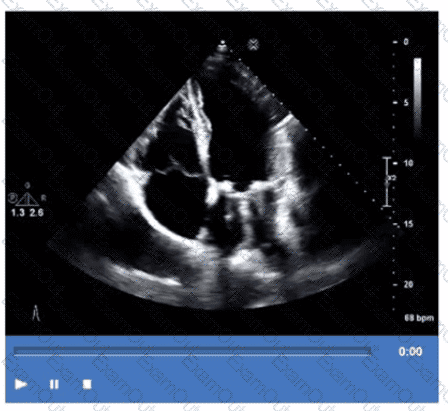

Which finding is demonstrated in this video?